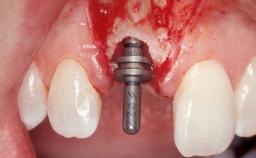

Immediate Flapless Placement of an Implant in a Maxillary Left Central Incisor Site

A 29-year-old female patient presented for treatment to replace the upper left central incisor tooth with an implant- supported restoration. The tooth had been intermittently symptomatic for the previous 12 months. The tooth had originally suffered trauma about 15 years previously. Several endodontic treatments had been performed, including an apicectomy procedure to retain the tooth. The patient was healthy and a non-smoker. She had reasonable expectations in regard to esthetic outcomes and the risk of marginal tissue recession following treatment. At medium smile, the gingival margins of the upper teeth were visible, with a display of 3 to 4 mm of the gingival margins. Gingival recession of tooth 21 and a discrepancy in the gingival levels between teeth 11 and 21 was observable during normal speech and smile.

Placement Protocol Immediate implant placement

Tooth Site Maxillary incisor or canine

Socket Morphology Single-root socket

Socket Integrity Damage to one or more bone walls